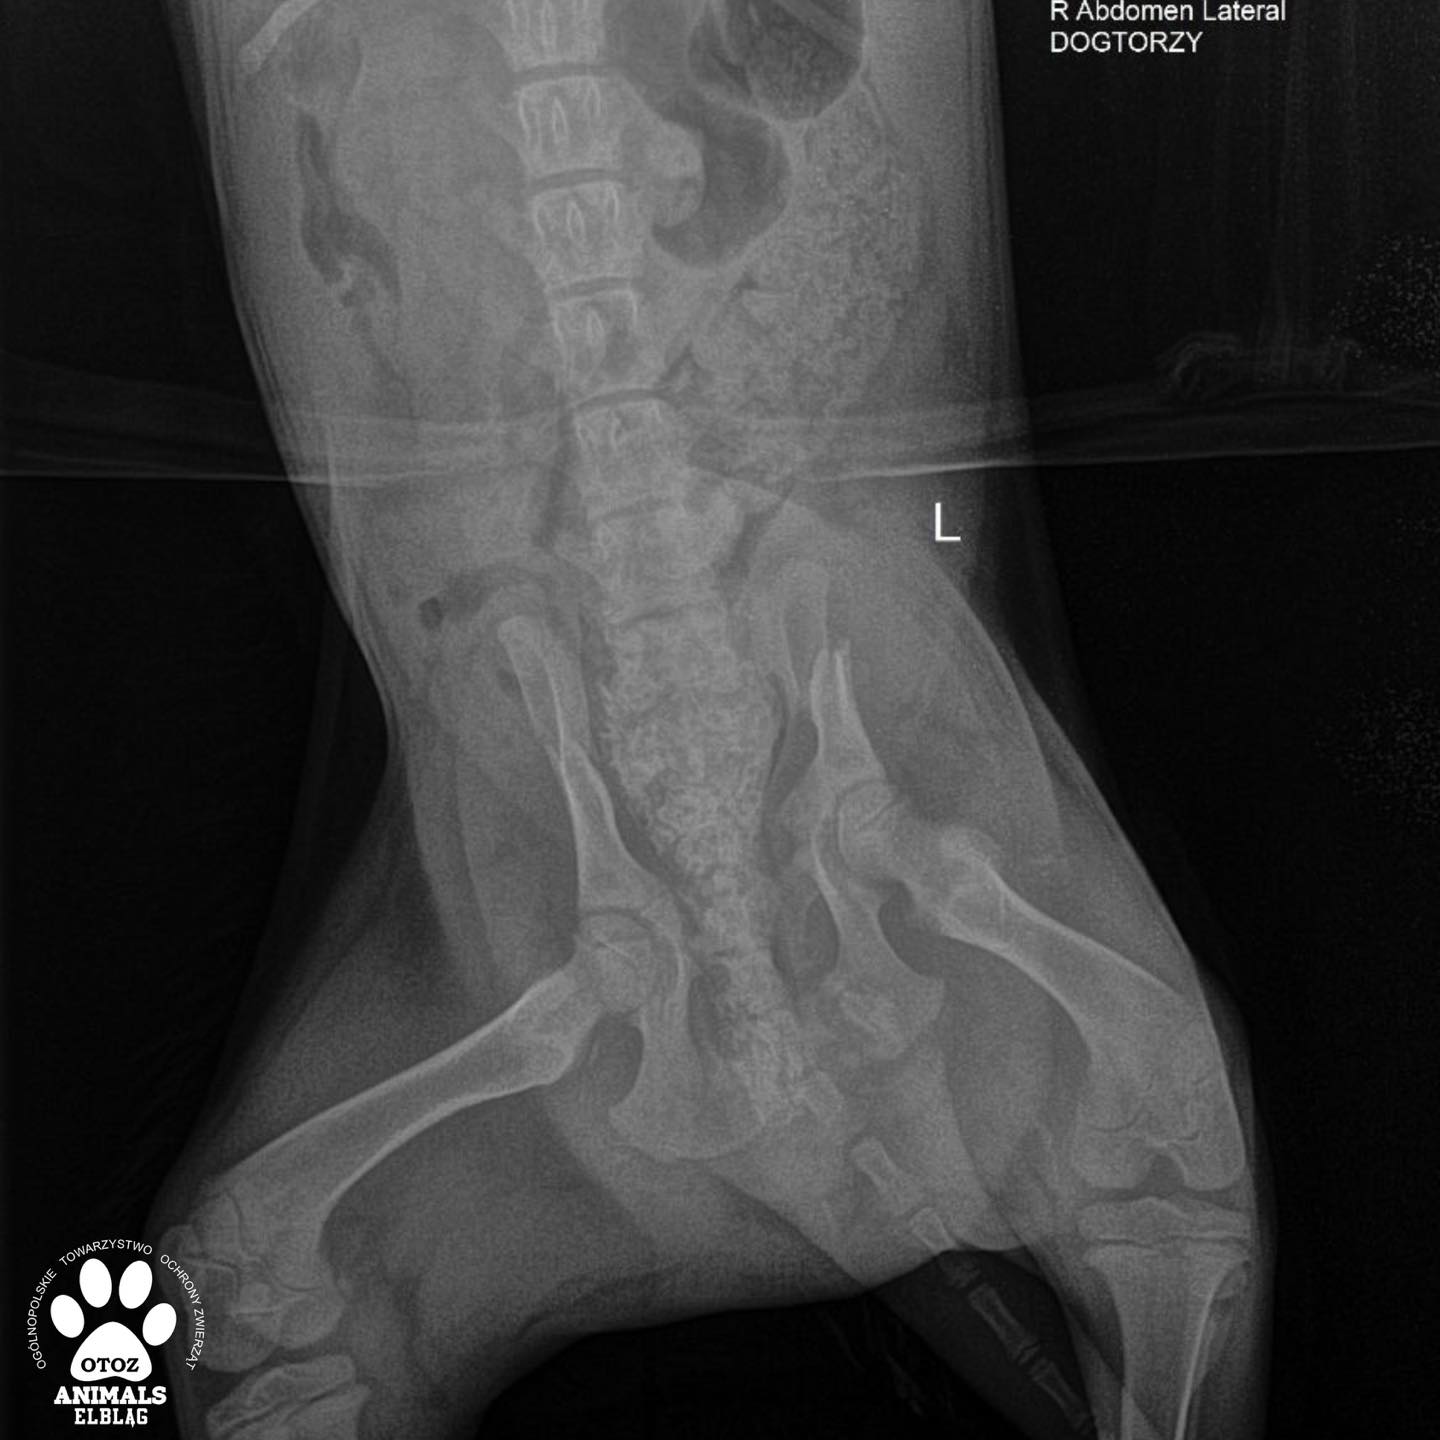

Suczka Nastka jest już po operacji. Jej życiu nie zagraża już niebezpieczeństwo - dochodzi do zdrowia w schroniskowej izolatce. Will w wyniku wypadku komunikacyjnego doznał złamania kości biodrowej, łonowej i kulszowej.

Dzisiaj czeka go bardzo poważny zabieg - osteosynteza z użyciem płyty. Koszt tego zabiegu to 3000 zł. Gorąco prosimy Was o pomoc w opłaceniu tej faktury…